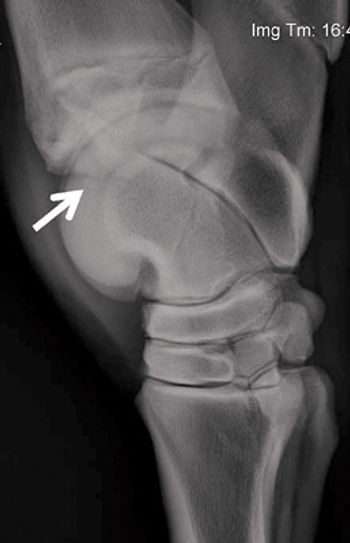

Although fairly prevalent in 2-year-olds, this common inflammatory condition of the cannon bone can affect any Thoroughbred racehorse in training and lead to more serious injury further on in a horse's career.